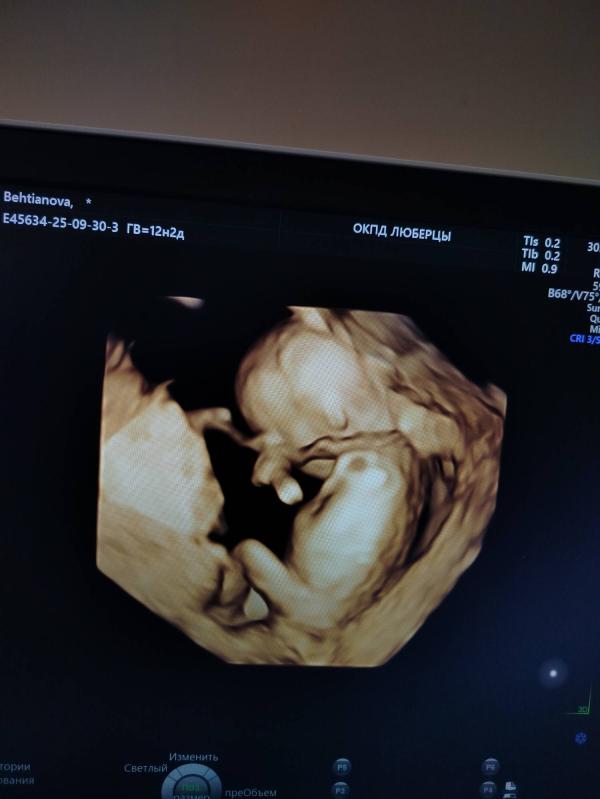

Сегодня был 1 скрининг, 12.2 недели. Очень волновалась, славу Богу все хорошо🥹

Фотку распечатать не удалось, зато дали сфотографировать, даже в 3D формате😍

Не могу налюбоваться 🥹

Тут увидела многие кидают фото с узи и гадают по строению головы какой будет пол🤣 Кого видите ? 😁

Похоже на девочку, но не факт конечно 🙈